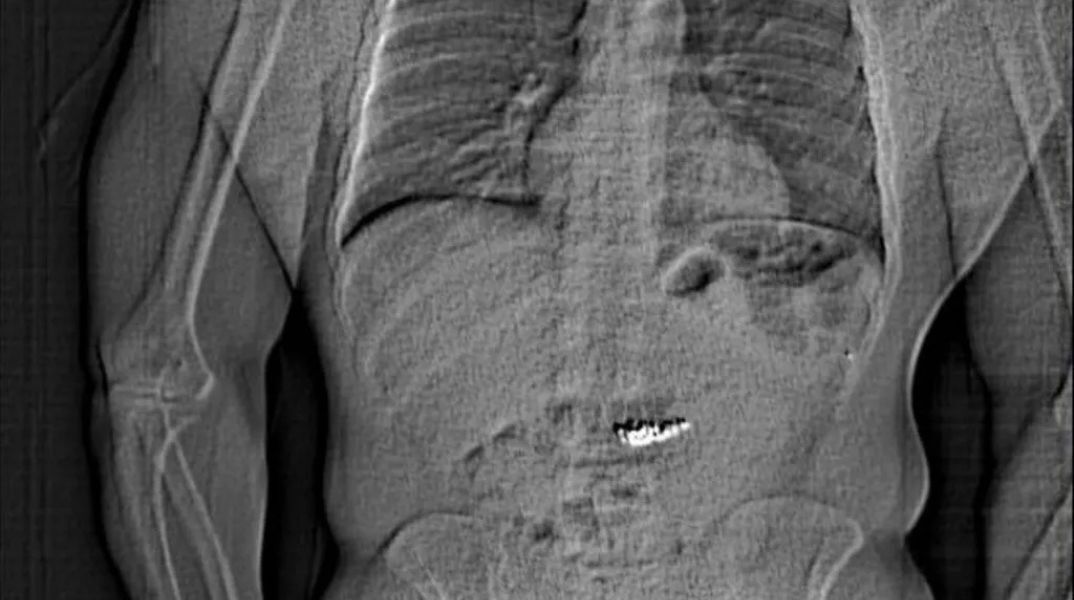

Η αστυνομία αργότερα έδωσε στη δημοσιότητα μια ακτινογραφία που φαίνεται να δείχνει ένα ξένο αντικείμενο στην κοιλιακή χώρα ενός ατόμου.